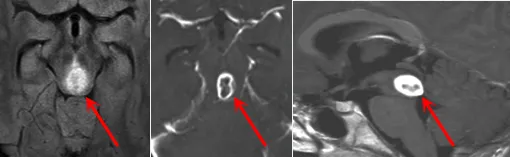

术后影像学复查结果

手术几天后按计划进行,巴教授团队经过数小时精心操作成功切除肿瘤。术后病理检查显示为WHO Ⅲ级间变性星形细胞瘤(Anaplastic Astrocytoma)。通过巴教授15年长期随访,马修现已顺利进入成年阶段。尽管童年时期遭遇重大疾病,但成功的手术治疗为他争取了完整的少年和青年时期。目睹目前笑容满面、精神饱满的马修,父母深感庆幸当年的治疗选择不仅避免严重后遗症,更挽救了他的生命。术后影像学检查结果显示良好。